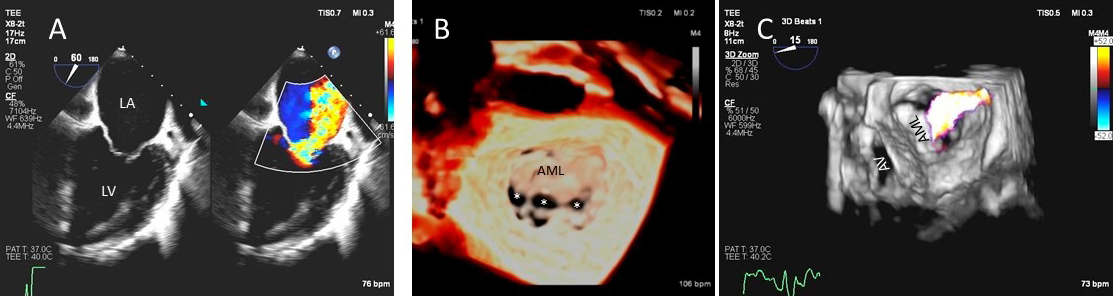

Besides prolapsing or flail scallops, MR jet may also originate between individual scallops. This occurs more commonly between the posterior leaflet through cleft like indentations that sometimes extend to the mitral annulus. This origin of MR can be very difficult to diagnose on 2D TTE or TEE (Fig. 2A–C). 3D color Doppler further assists in confirming jet origin at the site of suspected leaflet pathology/ies including presence of mitral valve cleft like indentation/s. Presence of calcification on the annulus and leaflets and in the subvalvular apparatus further assists surgeon in planning repair [21]. Visualization of the valve from the LV perspective adds further information on leaflet morphology, coaptation and regurgitant site/s particularly if jet originates from mitral valve clefts. Optimal visualization of the MR jets using real-time 3D TEE leads direct guidance for catheter movement and positioning of the implanted device(s) capturing the opposing sides of anterior and posterior mitral leaflet scallops during catheter based MV interventional procedures [22].

Fig. 2.Mitral leaflet Cleft. (A) TTE short axis at the mitral valve level showing posterior mitral cleft. (B, C) Isolated cleft within the P2 segment of the posterior leaflet (associated with mitral regurgitation) on 3D TEE and TTE short axis views. AML, anterior mitral leaflet; PML, posterior mitral leaflet.

As opposed to degenerative MR, mitral valve leaflets in secondary MR may be normal but MR results from leaflet mal-coaptation due to a dilated mitral annulus as in dilated cardiomyopathy or due to tenting of mitral leaflets due to LV infarct remodeling causing outward displacement of papillary muscles and tethering of chordae attached to these papillary muscles. Mal-coaptation may be along the entire mitral leaflet coaptation plane mostly in functional MR (Fig. 3A–C) or localized to some scallops commonly seen at the P3 scallop of the mitral valve in the presence of a remodeled infero-posterior myocardial infarction causing tethering of the chordae to P3 scallop (ischemic MR).

Fig. 3.Functional Mitral regurgitation. (A) Transesophageal echocardiogram biplane view shows a dilated LV with mitral valve coaptation point displaced into the LV and central MR jet. (B) 3D TEE showing central mitral leaflet malcoaptation (white asterisks). (C) 3D TEE surgical view of the mitral valve showing severe central mitral regurgitation. LA, left atrium; LV, left ventricle; AML, anterior mitral.